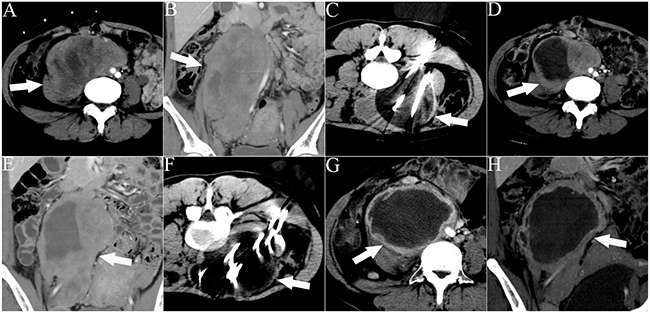

Figure 3: CT images of a 32-year-old woman who underwent 2 sessions of cryoablation for a recurrent RPS. The patient experienced abdominal distension and pain for 1 month. The white arrows indicate the lesion. The white lines indicate the cryoprobes. The dark area around the cryoprobe is the ice-ball. A, B. Cross-sectional and coronal contrast-enhanced CT images illustrating the lesion with an abdominal aorta push. C. The first session of cryoablation using 11 cryoprobes. D, E. Cross-sectional and coronal contrast-enhanced CT images acquired 1 month after the first session of cryoablation illustrating necrosis of the lesion and lesion shrinkage. F. The second session of cryoablation using 10 cryoprobes. G, H. Cross-sectional and coronal contrast-enhanced CT images acquired 1 month after the second cryoablation session illustrating significant necrosis of the lesion and lesion shrinkage.